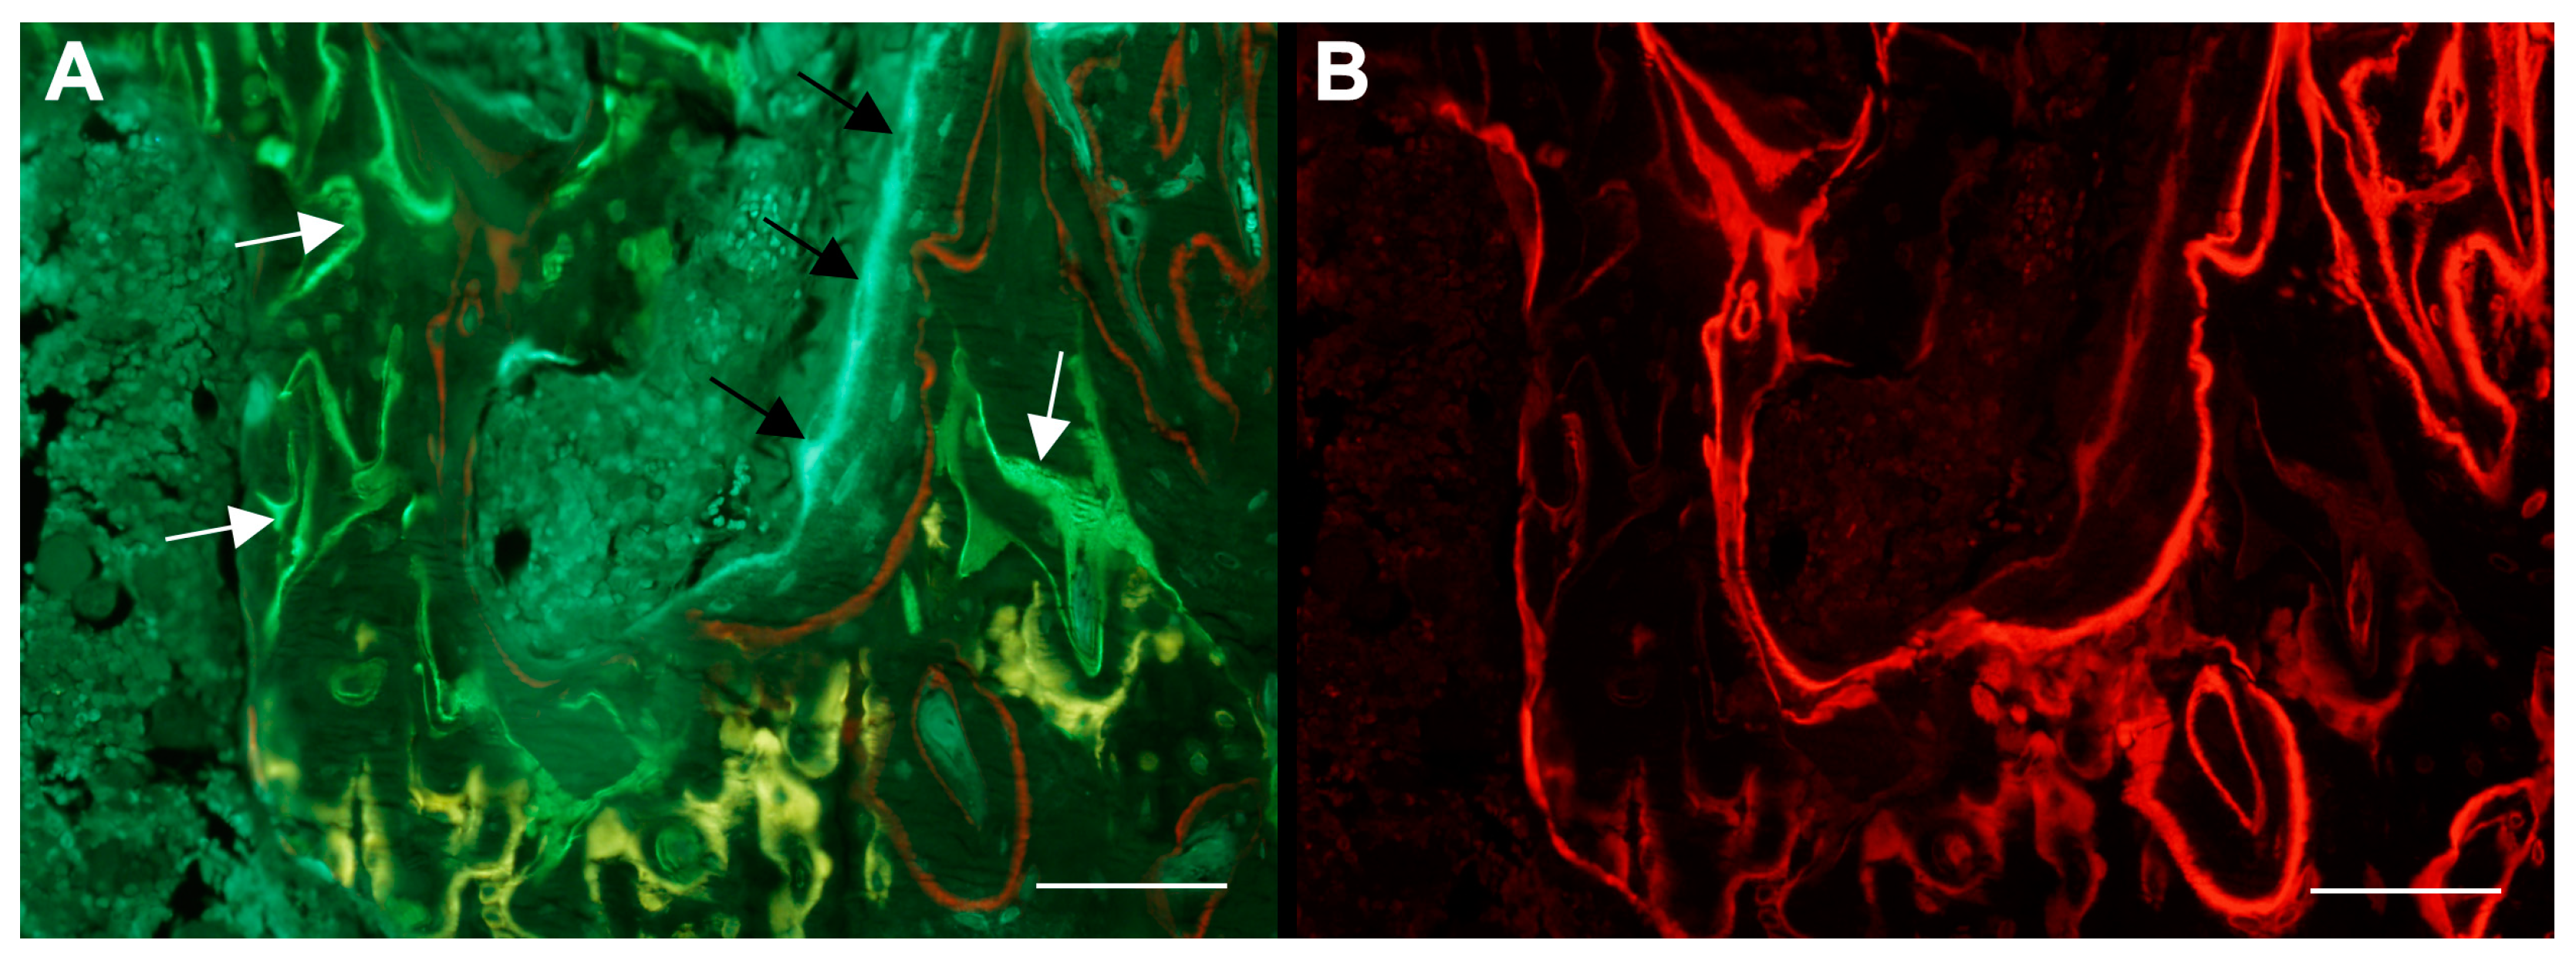

The visualization of fluorescent bone labels can be complicated by the pale green autofluorescence that calcified bone emits under ultraviolet light (Figure 6).

Figure 6.

Dynamic bone histomorphometry at the proximal tibial metaphysis of a rat with botulinum toxin (BTX)-induced hind limb disuse and treated with parathyroid hormone 1–34 (PTH) and growth hormone (GH) in combination [35]. The rat was injected subcutaneously with tetracycline (yellow), calcein (green), and alizarin (red). (A) Note how the pale green autofluorescence (black arrows) can be distinguished from the bright green calcein fluorochrome labels (white arrows). (B) Red HC-mFISH single-band filter. A red single-band filter can be used to enhance the visibility of alizarin fluorochrome labels if they appear dim. Scale bars = 100 μm.

However, this can be overcome by increasing the camera exposure time or using fluorochromes in sharp contrast to pale green. Alternatively, narrow bandpass filters can be used. Tetracycline (yellow), alizarin (red), and calcein (green) were used in the experiment depicted in Figure 6, and these fluorochromes are relatively easy to distinguish from the pale green autofluorescence emitted by calcified bone. Alternatively, a red HC-mFISH filter (AHF Analysentechnik, Tübingen, Germany) for alizarin labels and a BV-2A filter (Nikon, Tokyo, Japan) for calcein labels can be used as needed to more easily distinguish these bone-specific fluorochromes. Similarly, other filters exist for fluorochromes with different emittance spectrums.